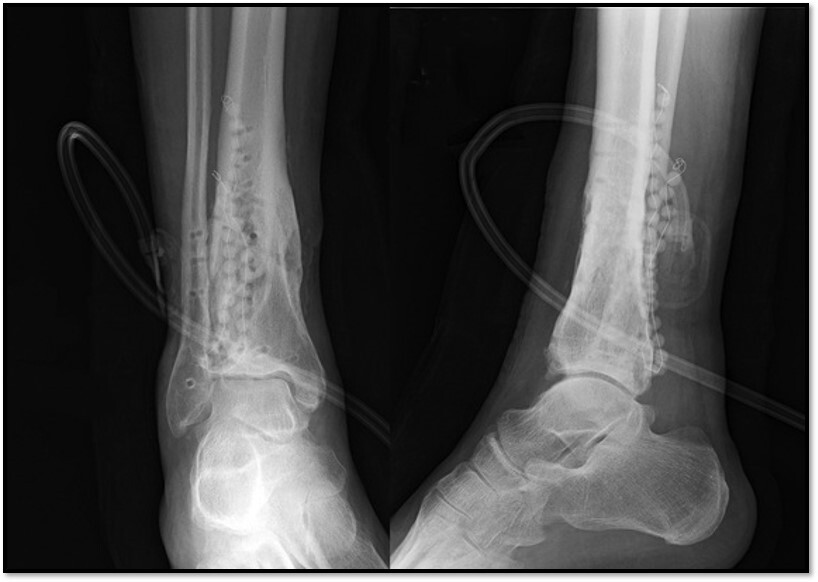

What is this showing here?

A

Antibiotic leads